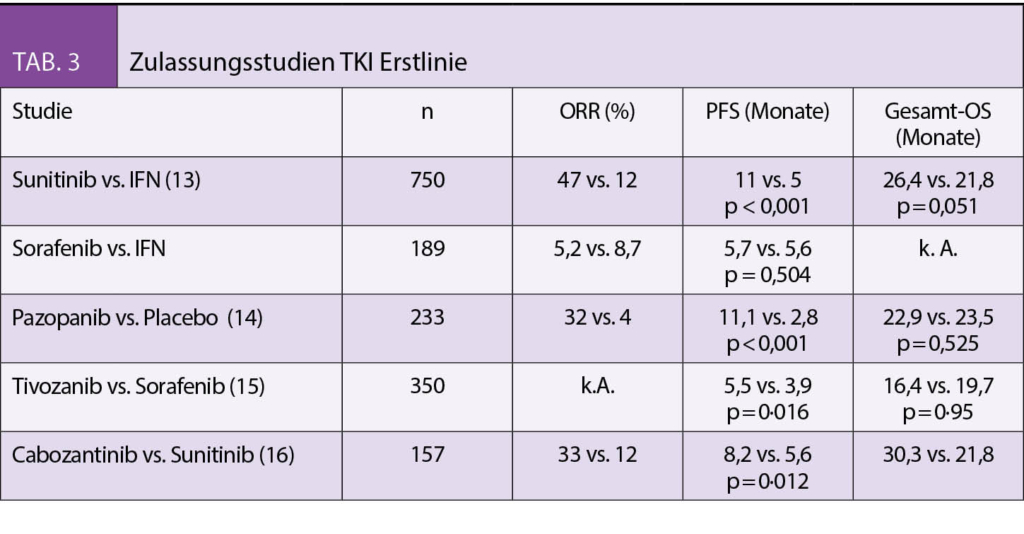

In der Vergangenheit galt die Nephrektomie vor Systemtherapie als obligater Standard, begründet durch positive prospektive und retrospektive Studienergebnisse (8-9). Die Daten aus der in 2018 veröffentlichten CARMENA Studie (prospektive Nicht-Unterlegenheitsstudie bei Patienten mit intermediärem und hohem Risiko) zeigten hingegen, dass die alleinige TKI Therapie mit Sunitinib der Tumornephrektomie plus Sunitinib nicht unterlegen war. (10) Diese Ergebnisse decken sich mit den Daten der SURTIME Studie. (11) Aktuell erfolgt die palliative Tumornephrektomie nur noch bei selektionierten Patienten. Eine frühzeitige interdisziplinäre Vorstellung ist notwendig (Tab. 3).

Erstlinientherapie des meta-stasierten Nierenzellkarzinoms

In den letzten Jahren wurden viele neue Substanzen zugelassen. Die TKIs Sunitinib, Pazopanib und Tivozanib zeigten dabei einen signifikanten Vorteil im PFS, jedoch nicht im OS (13-15). Die Substanzen wurden in den Studien mit dem damaligen Standard Interferon-alpha bzw. Placebo verglichen. Eine publizierte Phase-II Studie verglich Cabozantinib mit Sunitinib und konnte für die intermediären und Hochrisikopatienten einen signifikanten PFS Benefit sowie einen Trend zu einem besseren OS zeigen (16). Die alleinige Therapie mit einem TKI in der Erstlinie ist seit den positiven Studienergebnissen mit Immuncheckpointinhibitoren nicht mehr erste Wahl. Prospektive randomisierte Studien mit Nivolumab, einem anti-PD-1 Antikörper in Kombination mit Ipilimumab, einem anti-CTLA-4 Antikörper (CheckMate 214) sowie mit Pembrolizumab, einem Anti-PD-1 Antikörper und dem TKI Axitinib (KEYNOTE-426) – jeweils gegen Sunitinib randomisiert – zeigten in beiden Fällen einen signifikanten Vorteil sowohl im Tumoransprechen, im PFS und auch im OS. Nivolumab/Ipilimumab zeigte diesen im Gegensatz zu Pemprolizumab/Axitinib nur für die intermediären und Hochrisikopatienten (17-18). In der Schweiz können Patienten derzeit in eine klinische Phase II Studie (SAKK 07-17), die eine sequentielle Therapie mit Nivolumab und Ipilimumab in der Erstlinie untersucht, eingeschlossen werden. Mehrere Zentren in der Schweiz nehmen teil (Tab. 4).